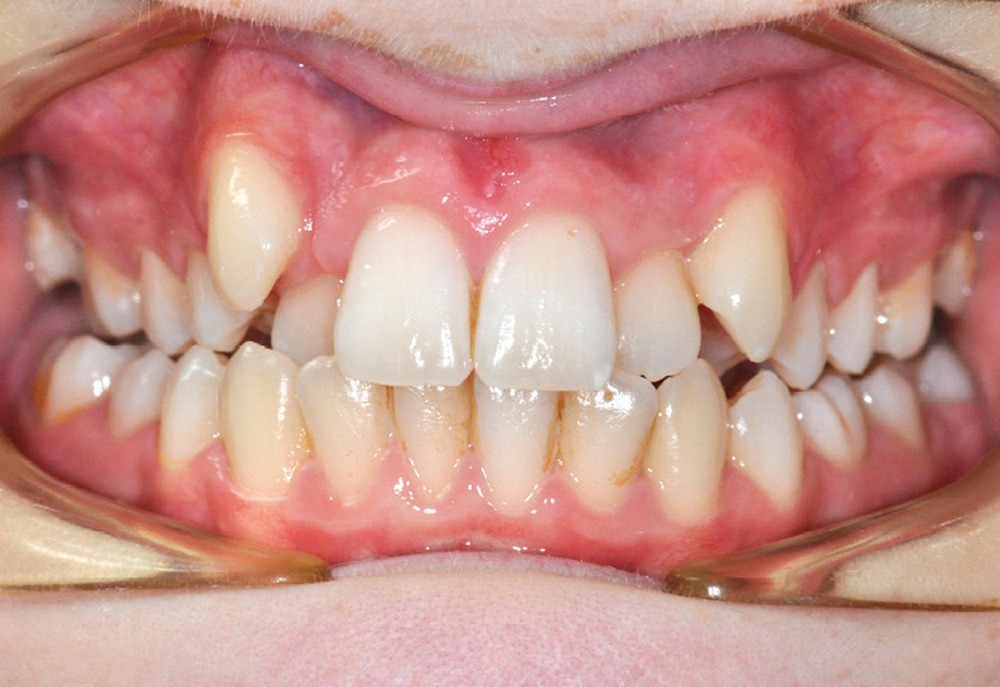

Julien nous consulte à l’âge de 11 ans et 4 mois pour des raisons essentiellement esthétiques, afin d’améliorer l’alignement de ses incisives maxillaires (fig. 1a-d) ; son chirurgien-dentiste l’a toutefois alerté sur un problème d’évolution des 35 et 47, dont l’inclusion a été mise en évidence lors d’un contrôle radiographique (fig. 1e).

Le patient présente des lèvres fines et un profil orthofrontal avec des pommettes effacées. Le sourire est inesthétique du fait de l’encombrement maxillaire, mais aussi en raison de la contraction asymétrique de la lèvre inférieure.

L’examen intra-oral met en évidence une occlusion inversée bilatérale ainsi qu’un manque de place conséquent pour les incisives latérales maxillaires en palato-position et une infra-vestibulo-position de 13 et 23. Le patient est déjà en denture adulte jeune, hormis la persistance de la 75. L’occlusion est en classe II, plus marquée du côté droit sans engendrer de déviation des médianes incisives, d’où une mésio-position plus importante de la 13 par rapport à la 23.